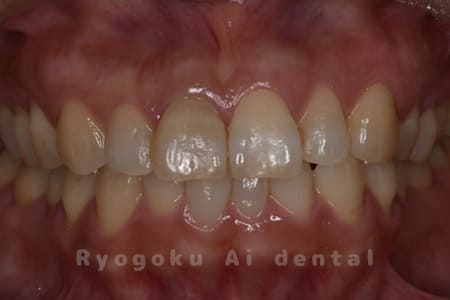

Case04

-

- 原因

- 失活による歯牙変色

- 治療内容

- ブリーチング+マイクロエンド+ダイレクトボンディング+ホワイトニング

- 治療費用

- 231,000円(ブリーチング55,000円+マイクロエンド77,000円+ダイレクトボンディング66,000円+ホワイトニング33,000円)

結婚式前に前歯を綺麗にしたいとのことでご来院された患者様です。根の状態も悪かったためマイクロスコープ下で根管治療を行い、ブリーチングの後にダイレクトボンディングで形態修正を行いました。

<リスク・副作用>

治療中もしくは治療後に急に痛みが出る場合があります。感染が強い場合には痛みが激しいことがありますので、その際は痛み止め、抗生剤を処方する場合があります。

また、ダイレクトボンディングは強い衝撃などにより欠けたりすることがある。経年的に劣化(変色)してくる可能性がある。